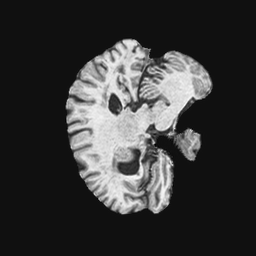

Exp. 3: Adult thorax data: To show the versatility of our approach we also apply it to adult thorax scans. For this experiment no organ specific training is performed but the whole volume is used. We evaluate reconstruction performance similar to Exp. 1 and prediction performance when is projected on an external plane, comparable to X-Ray examination using C-Arms. The latter provides insights about our method’s performance when applied to interventional settings in contrast to motion compensation problems. 60 healthy adult thorax scans were randomly selected, 51 scans used for and nine scans used for . Each scan is intensity normalised and resampled in a volume of with spacing . Using the Fibonacci sampling method, 25 sampling plane of size , evenly spaced between -50 and +50, were rotated over 500 normals. Training took approximately 20 hours for 60 epochs. Fig. 4c shows an example reconstruction result gaining 28dB PSNR with additional SVR. prediction takes approx. 20 ms/slice for this data.

Here we show for Exp. 1, Exp. 2, and Exp. 3 randomly selected examples of images that have been presented to the network (ground truth) compared to an image sampled at the predicted location.

In these experiments, we present a ground truth (GT) image to the network to estimate the respective transformation parameters needed to reorient the slice in its correct world co-ordinates. Using the transformation parameters, we generated a slice from the 3D atlas in the location where the network has predicted that slice should be (denoted as SVRNet).

The slices are compared side-by-side to give a visual representation of “where the slice really is” and “where the network thinks the slice is”.

0..5.3 Exp. 3:

We replicated the experiment on adult thorax data without specifically segmented organs. This approach was applied to CT acquisition, shown in Fig 13 and 14, as well as Digitally Reconstructed Radiographs generated using Siddon-Jacobs Ray Tracing shown in Fig. 16.